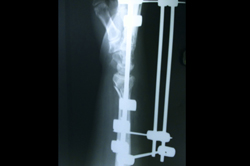

Periprosthetic Fracture THR